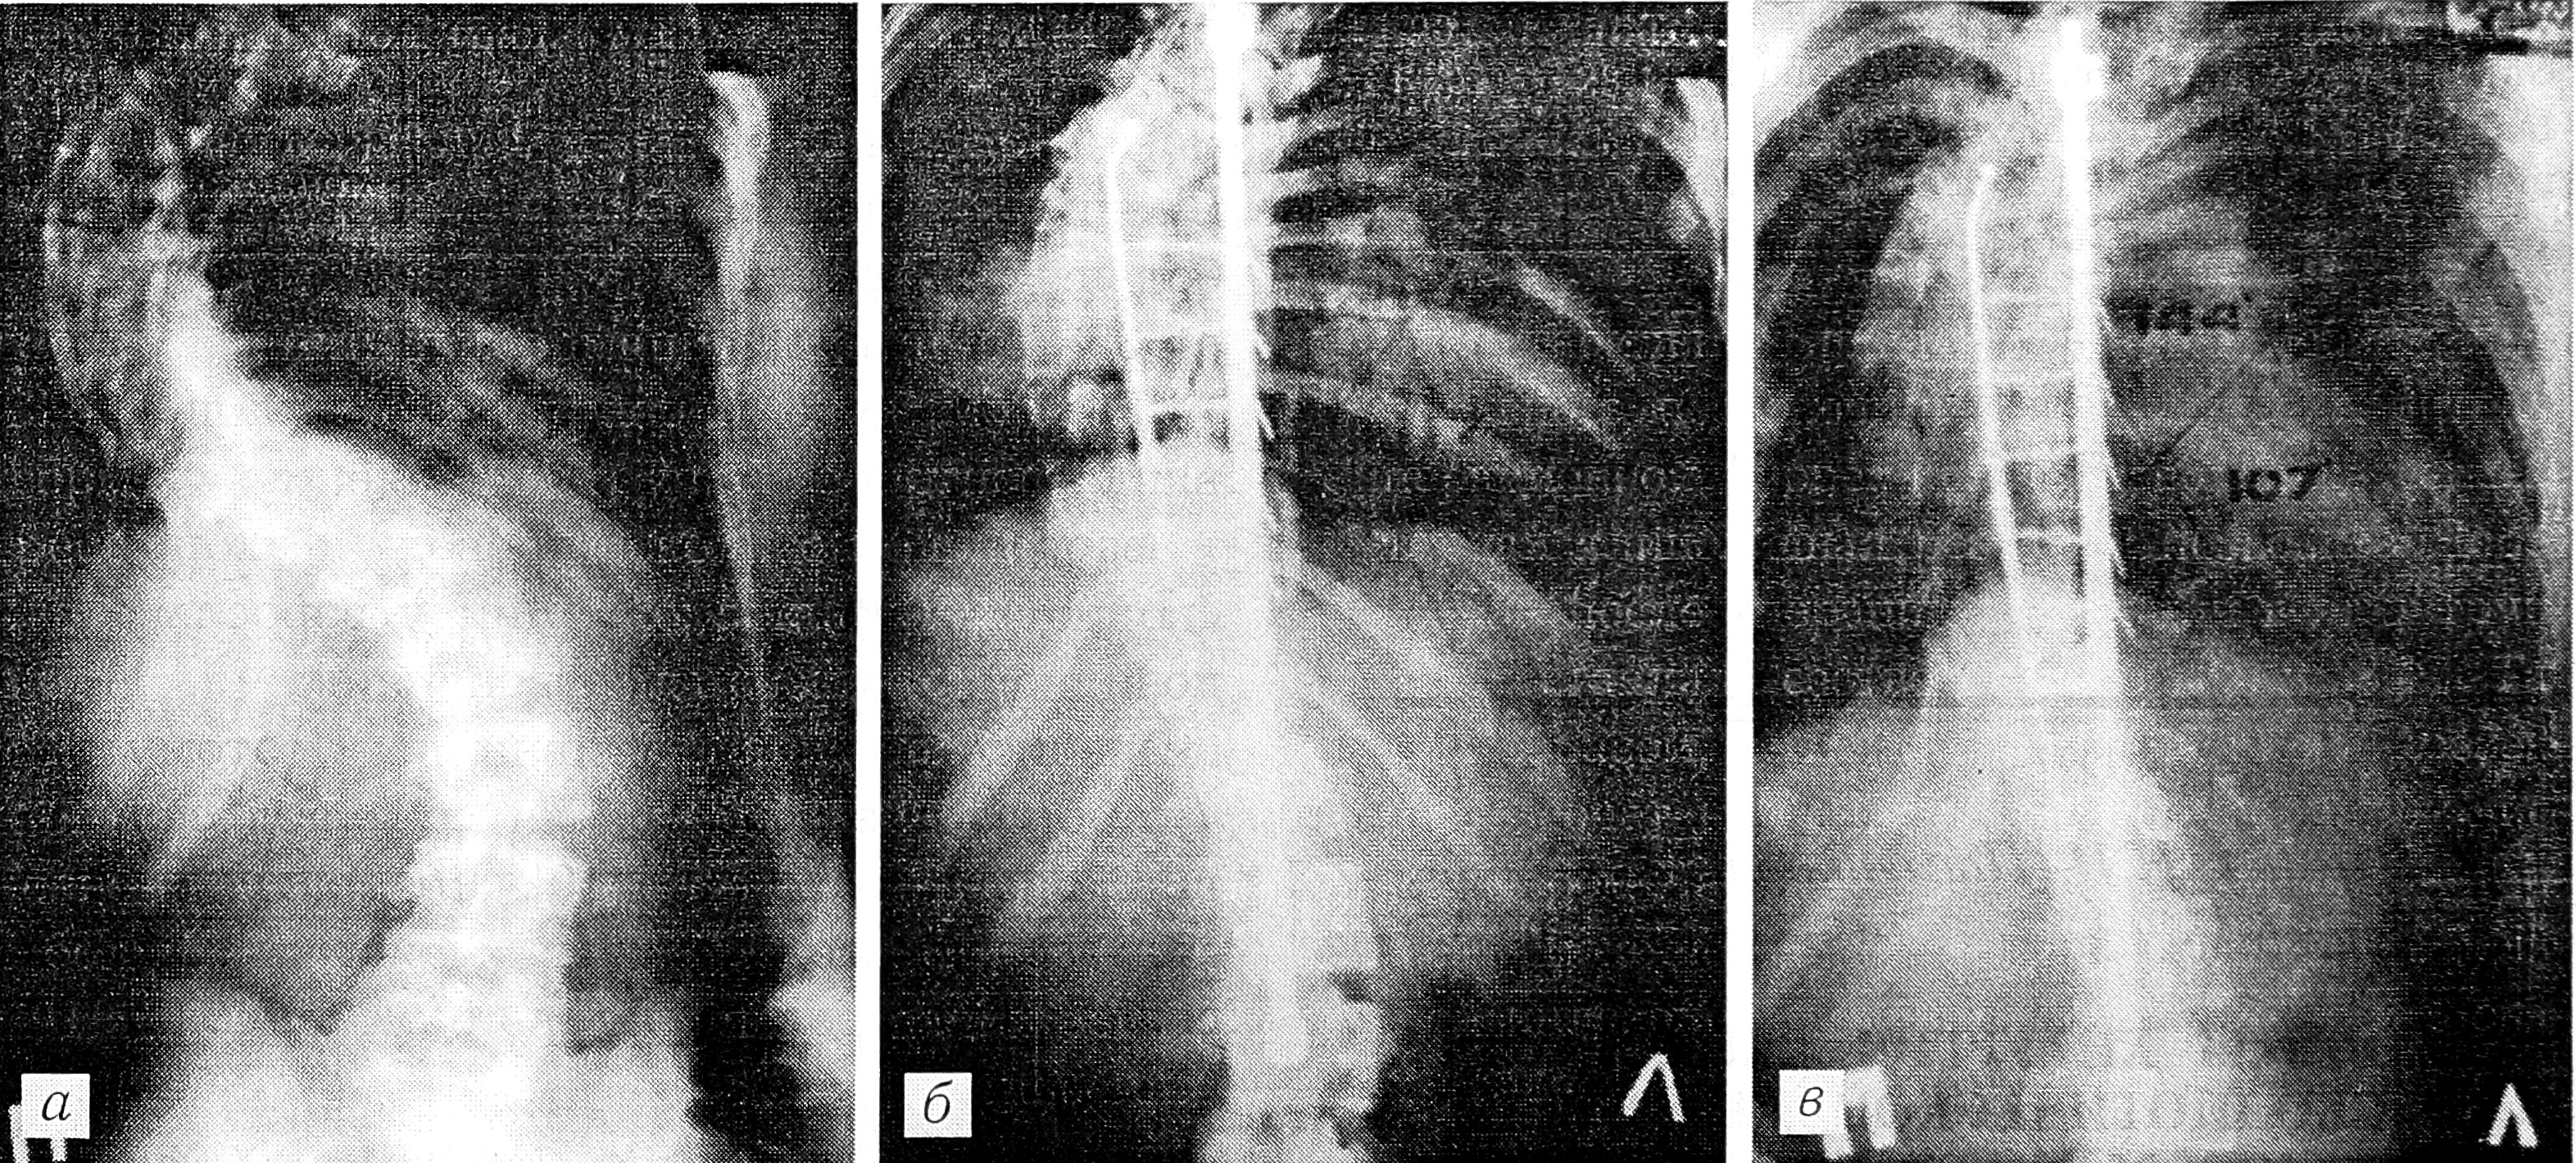

Для иллюстрации приводим рентгенограммы одной из больных 4-й группы.

Рентгенограммы больной С. 14 лет. Диагноз: диспластический правосторонний грудной сколиоз IV степени. Произведены: сегментарная клиновидная резекция тел позвонков на вершине искривления, коррекция и фиксация позвоночника дистрактором Харрингтона с боковой тягой.